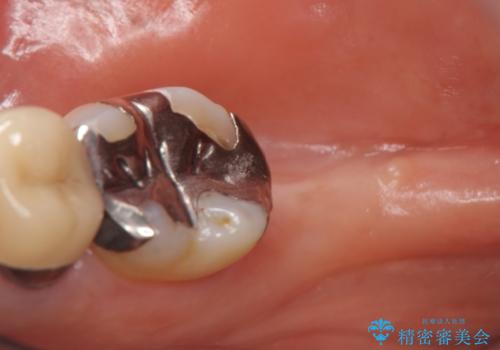

- 右下7番にインプラント治療を行った症例です。

CT撮影を行い状態を確認後、インプラント(ストローマン)の埋入(一次手術)を行いました。

インプラントと骨の定着を待った後に二次手術を行い、カスタムアバットメント、オールセラミッククラウンによる補綴を行いました。